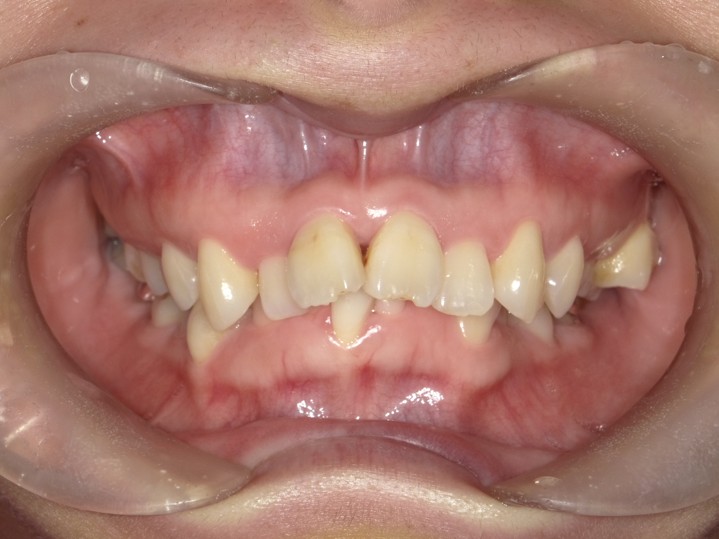

矯正治療・インプラント治療・セラミック治療の症例紹介(三隅歯科クリニック)

症例詳細

| 主訴 | 30代女性 顎関節が痛い。見た目も気になる |

| 治療内容 | 矯正治療を行いました。 |

| 治療費 | 1,700,000円(税込み) |

| 治療期間 | 3年(矯正治療期間 2年半) |

| 治療回数 | 40回 |

| 想定されたリスク | 術前に精密な診査診断とシミュレーションを行い、インプラントを適正なポジションに埋入しておかないと、インプラント自体が矯正治療の邪魔になるリスクがあった。 |